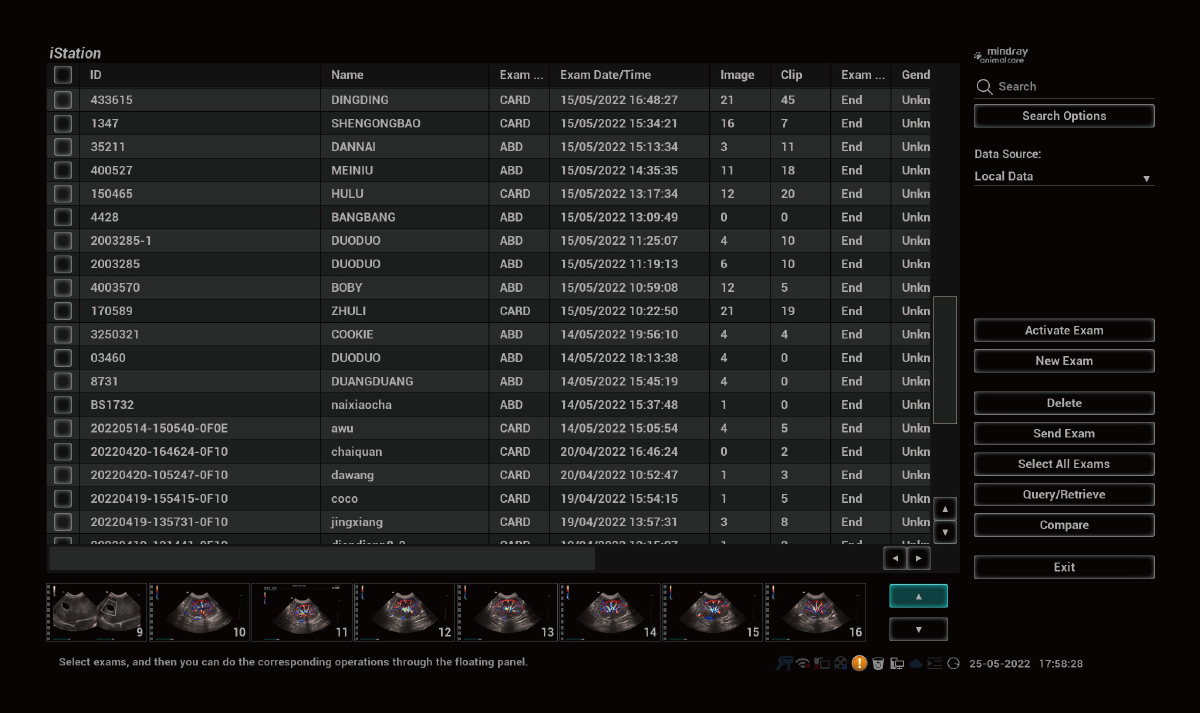

1iEstación

Sistema completo de gestión de información animal.